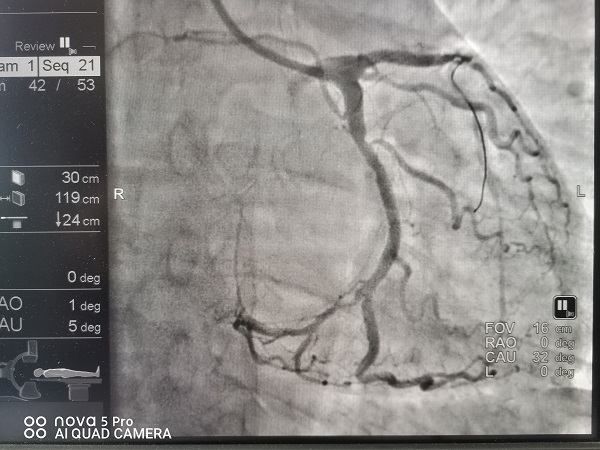

宜春学院第一附属医院 万载县人民医院心血管科涂小明主任正在总查房,突然收到胸痛中心远程会诊提示,原来是经过胸痛中心培训的黄茅镇卫生院医生首诊之后已完成了心电图检查并确诊了急性心肌梗死,然后发出了远程胸痛病人预警,涂小明主任根据心电图结果再次确诊后立即启动介入导管待命,09:30救护车进入我院大门后绕行我院急诊科及心血管科直达导管室,手术人员紧密合作,消毒、铺巾、穿刺桡动脉、造影、进指引导管、09:46过导丝,D2B(D2W)时间仅16分钟!创造了我院介入导管室抢救急性心肌梗死新的记录!

D2B(或D2W)时间是指急性心肌梗死病人进入医院大门到球囊(或导丝)通过病人冠状动脉血栓的时间,是胸痛中心质量控制反应急性心肌梗死救治水平最重要的的一个指标,90分钟之内达标,平均水平在60分钟左右。